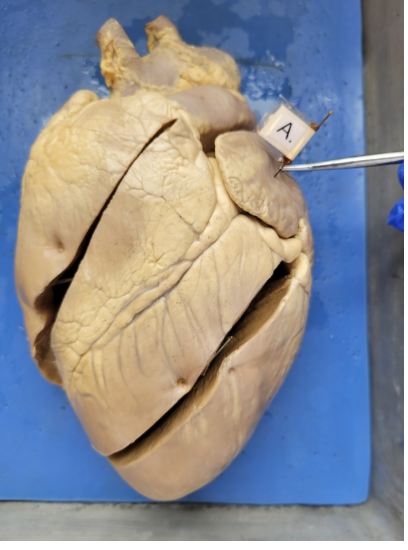

what is this

the left atrium